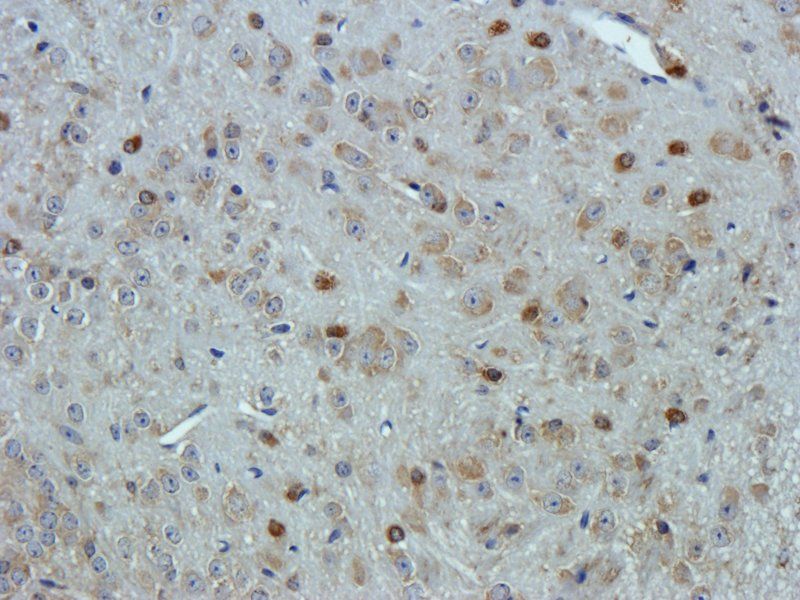

100 μg - PGP9.5 antibody [orb6713]Featured

ELISA, ICC, IF, IHC-P, WB

Human, Mouse, Rat

Rabbit

Polyclonal

Unconjugated

100 μg - FOXP3 antibody [orb34127]Featured